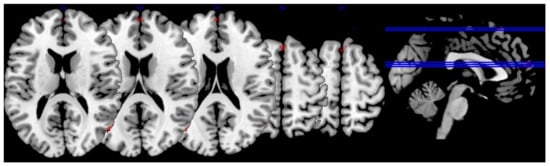

3.3. Lutein and Zeaxanthin Analysis

| Region | x | y | z | Extent | T-Score | Effect Size (r) |

|---|---|---|---|---|---|---|

| R superior lateral occipital cortex | 54 | −70 | 16 | 19 | 3.08 | 0.403 |

| 56 | −66 | 16 | * | 2.90 | 0.383 | |

| R inferior lateral occipital cortex | 56 | −68 | 12 | * | 2.94 | 0.387 |

| R middle frontal gyrus | 48 | 18 | 30 | 59 | 3.03 | 0.397 |

| R frontal pole | 0 | 60 | 16 | 31 | 2.93 | 0.386 |

| L cingulate gyrus | −2 | 4 | 24 | 30 | 2.85 | 0.377 |

| R cingulate gyrus | 4 | 2 | 30 | * | 2.56 | 0.343 |

| R angular gyrus | 60 | −50 | 38 | 15 | 2.84 | 0.376 |

| 62 | −50 | 34 | * | 2.81 | 0.373 | |

| R precentral gyrus | 62 | 12 | 8 | 9 | 2.82 | 0.374 |

| R superior frontal gyrus | 6 | 56 | 25 | 10 | 2.62 | 0.351 |